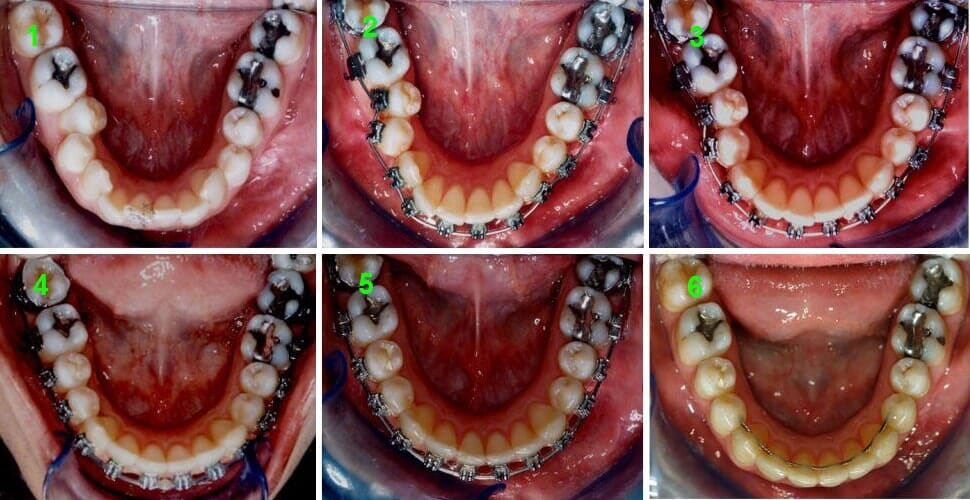

תמונות בתוך הפה

אחרי

תמונות מתוך הפה, אחרי

לפני

תמונות מתוך הפה, לפני

סידור קשתות השיניים